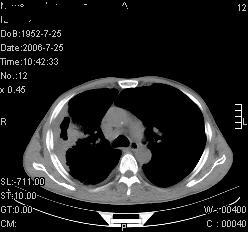

患者,男,54岁,咳嗦,咳痰20天。抗炎治疗2周。现esr76mm/h,目前患者症状明显好转,但发现两次ct片未见明显变化。两次分别做与7.25、7.31。第一次诊断右肺上叶炎症累计胸膜。大家看,从影像上内排除结核吗?

结核的可能性非常大,右上肺病变应该考虑干酪性肺炎。理由:

1.纵隔内多发淋巴结肿大。

3.虽经抗炎治疗肺窗病灶有所吸收、减小,但纵隔窗病灶形态、密度、范围无明显变化。如果是单纯的大叶性肺炎,“抗炎治疗2周,目前患者症状明显好转”病灶应该基本消散了,至少也处于吸收消散期,密度变淡、范围变小。同时本病例所示其内的密度不均匀,见多发大小不一空洞样影也不符合大叶性肺炎吸收消散期表现。

病灶特点:片状 索条 结节混杂影,部分融合,密度不均,广泛累及相应胸膜.

临床治疗;二周未吸收.但症状好转.

多考虑:肺结核.